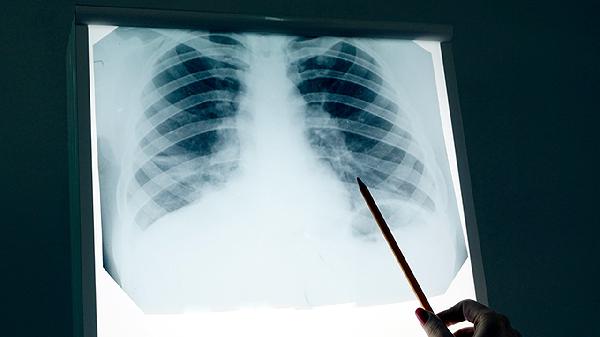

2、诊断背痛是否为肺癌引起,需结合影像学检查如胸部CT、MRI或PET-CT,以及肿瘤标志物检测。若怀疑骨转移,可进行骨扫描或骨活检。早期发现有助于提高治疗效果。